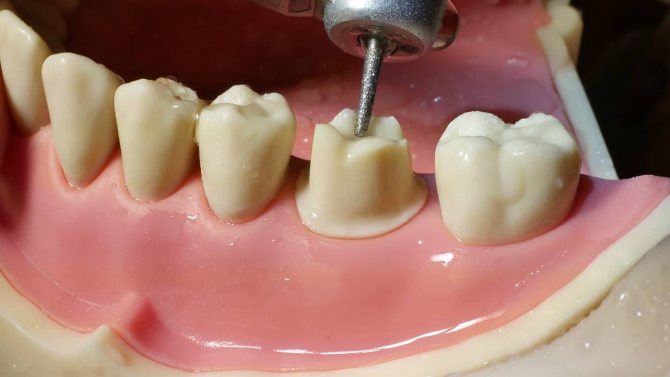

Основы диагностического воскового моделирования зубов для дальнейшего протезирования.

В некоторых случаях может потребоваться предварительное изготовление диагностической модели на основании слепков челюстных рядов пациента.

Полученный гипсовый образец подвергается тщательному осмотру и оценочному подпиливанию. В качестве инструментария для проведения операции применяются карборундовые фрезы либо алмазные боры.